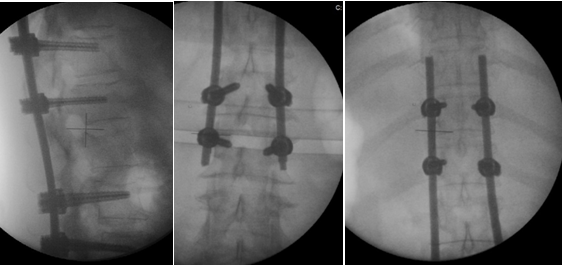

Wang considered PF as a good therapeutic option in type A thoracolumbar fractures, with significant differences between this technique and traditional open surgery, regarding incision size (Figure 1) blood loss, surgical time, hospitalization period, need for blood transfusion and postoperative analgesia. However, there were no differences between these two techniques regarding the radiological results obtained (Figure 2-6).13

Figure 3 Postoperative X-ray images after percutaneous fixation.